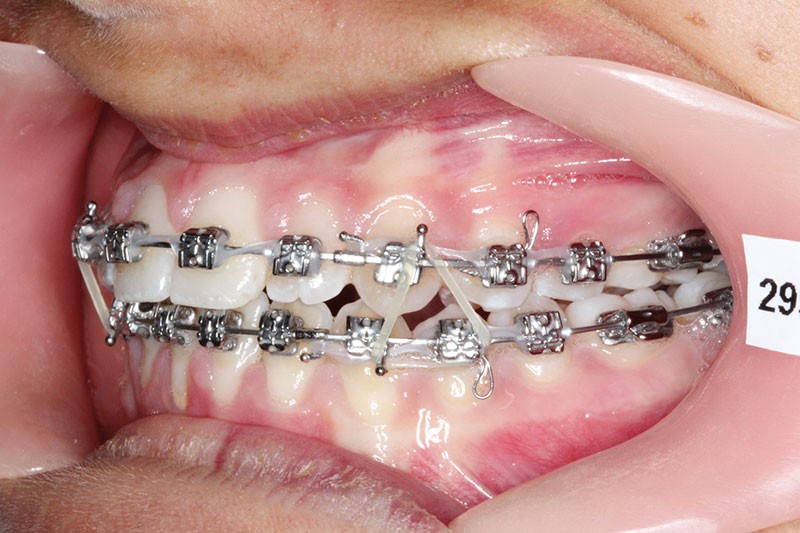

2e phase : mise en place du système multibague Carriere SLX (fig. 7 à 9)

Nous continuons le port des élastiques…